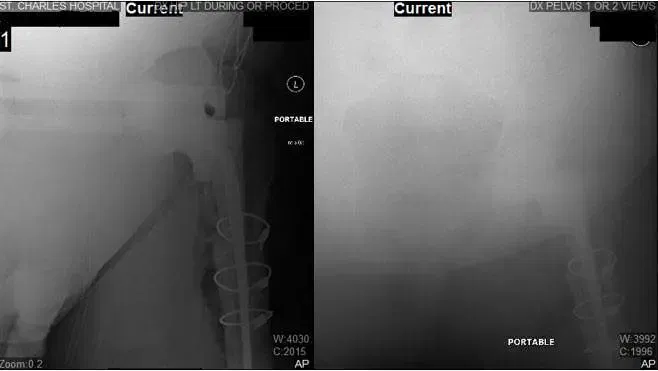

X-Rays of Left Hip during operation.

X-Rays show intraoperative changes including instalment of long stem THA, 2 screws setting the acetabulum, and cerclage wires surrounding the femur. X-Rays also show a nondisplaced transverse fracture of the proximal one-third femoral shaft.